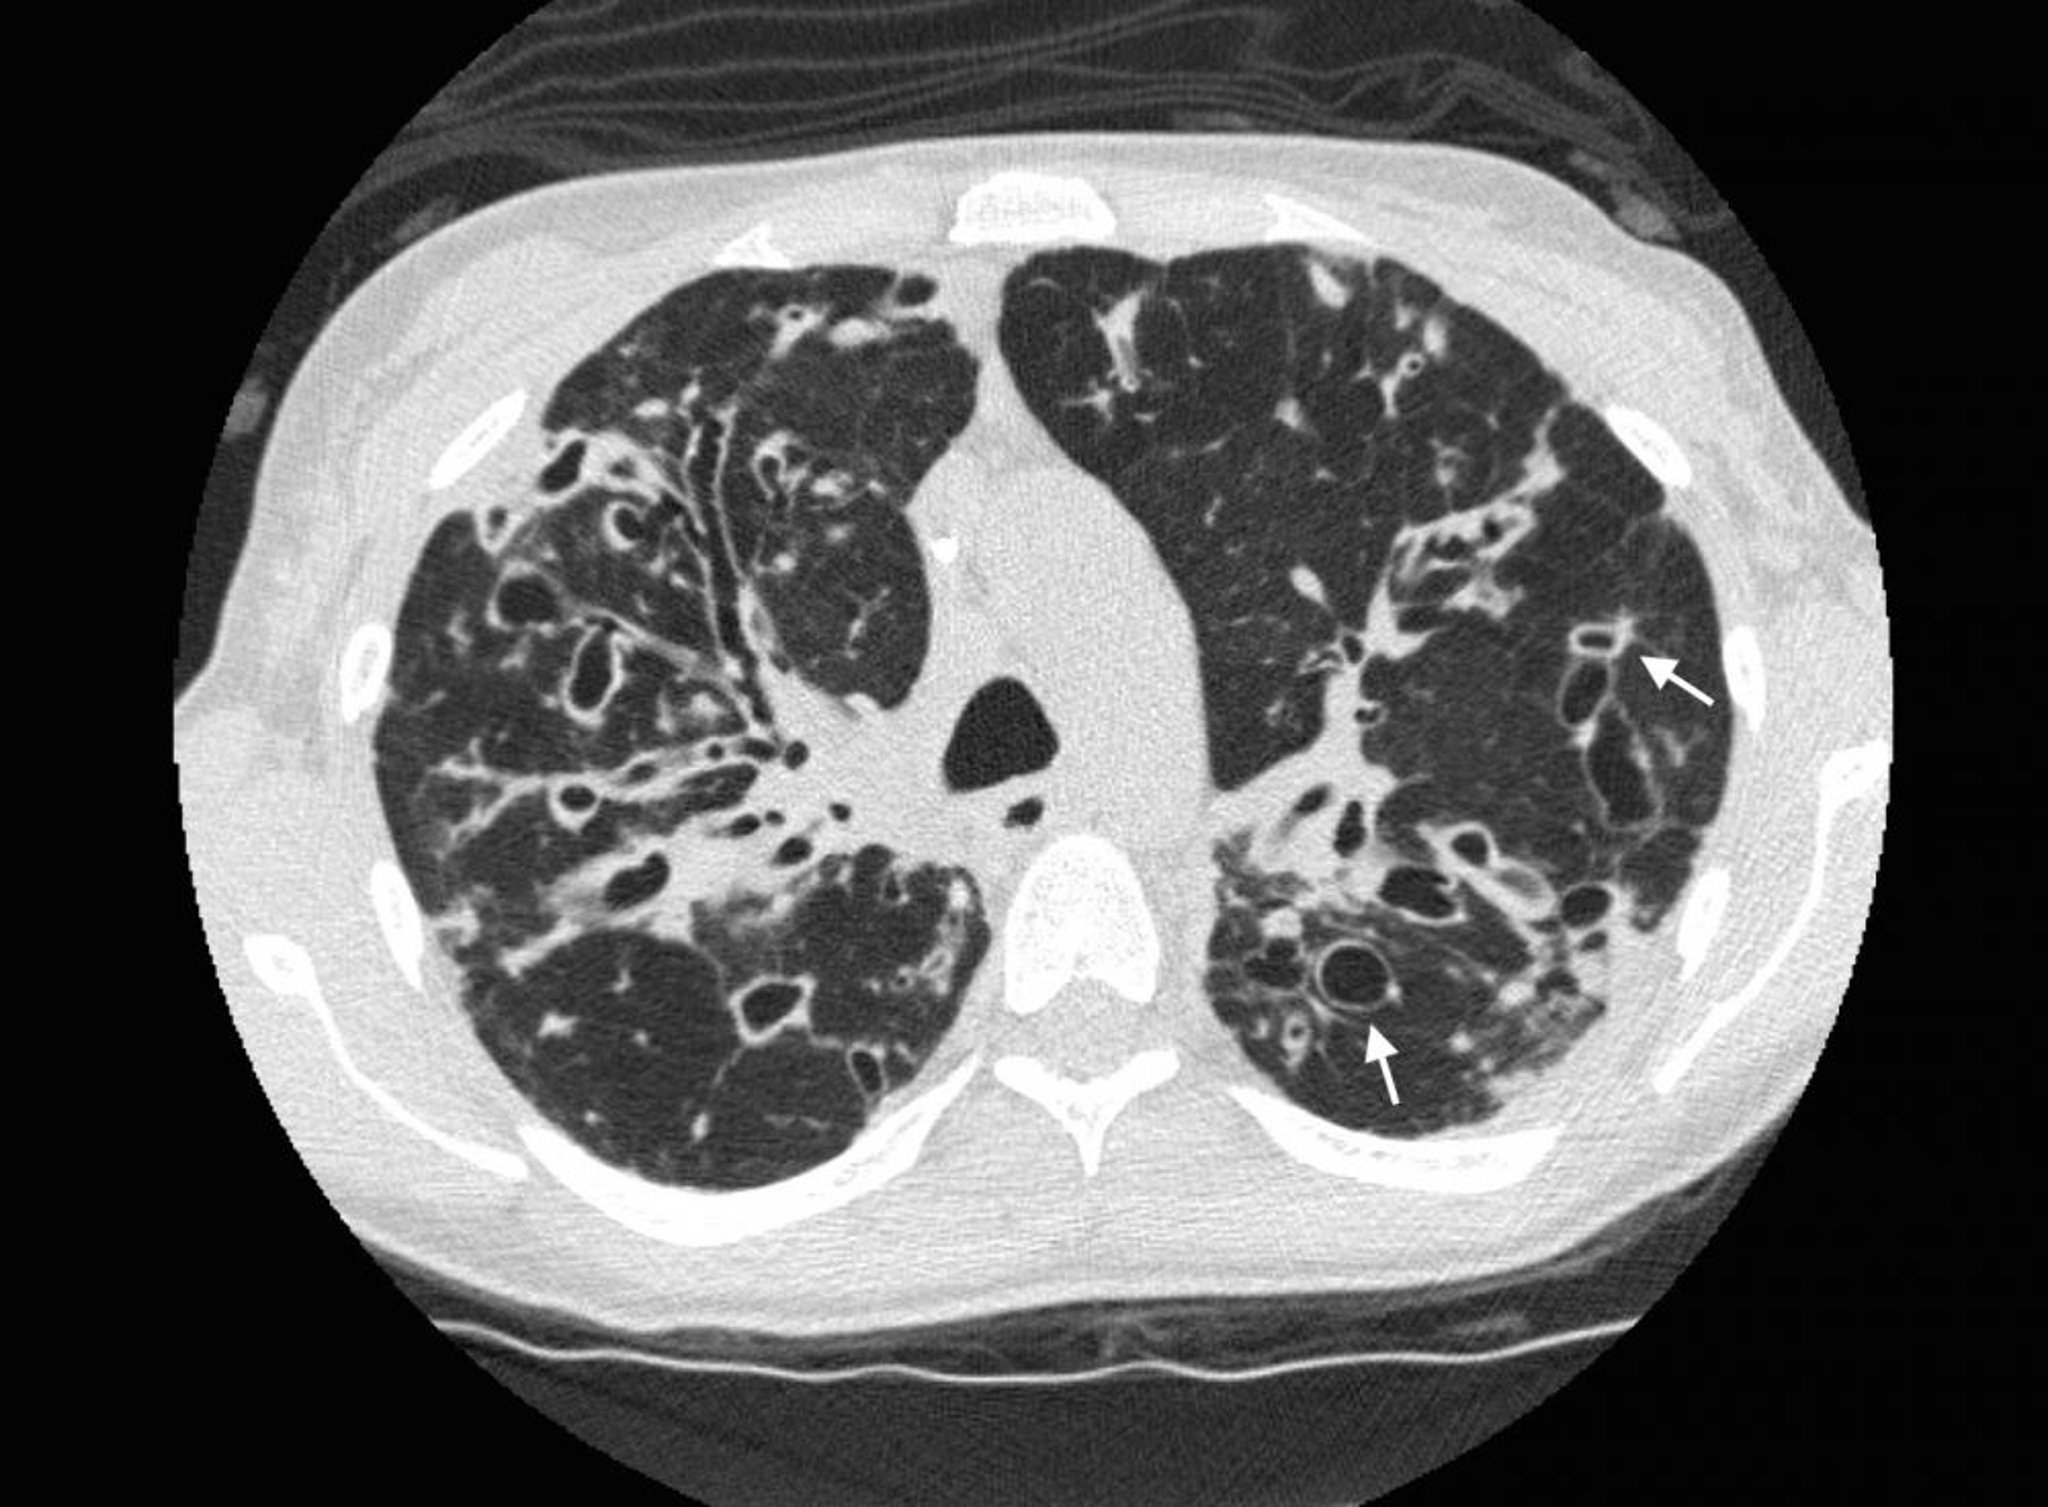

上肺野に,拡張した気道および嚢胞性変化を伴う重度の気管支拡張がみられる,嚢胞性線維症患者の胸部CT。矢印はsignet ring signを示し,拡張した気道(リング状の陰影)がより細い動脈(リングの上端)に接している。正常では,気道の径は近接する動脈と同じか,それよりも小さい。